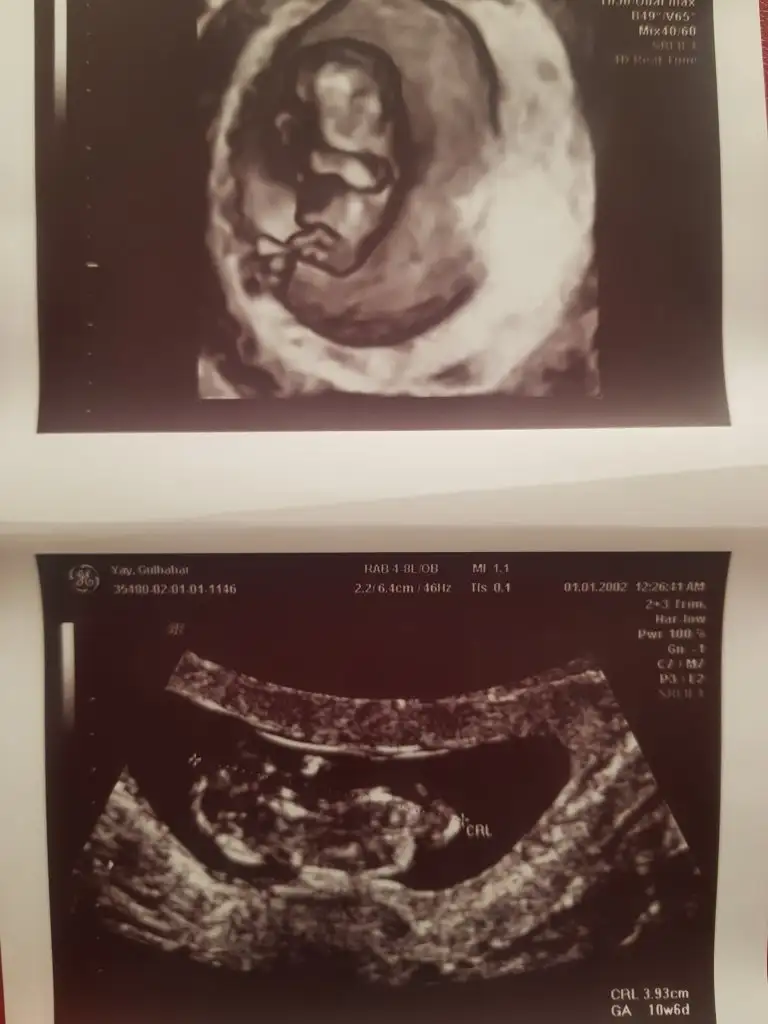

Bi de bu var ama bunda hiç görünmüyor sanki bi kere açtı bacağını onda da kordon vardı 🤣 14 dediğim de 13+4 ama geç mi kalmışız nub için acaba ?